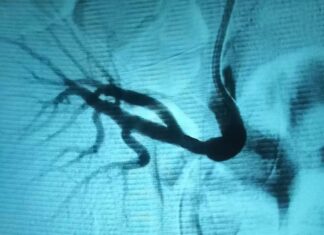

Випадок ендоваскулярного лікування стенозу ниркової артерії трансплантованої нирки в області судинного анастомозу

Хворий С. 22 р. направлений в ДУ «Науково-практичний центр ендоваскулярної нейрорентгенохірургії НАМН України» з приводу стенозу трансплантованої ниркової артерії.

З анамнезу: захворів на початку 2024...